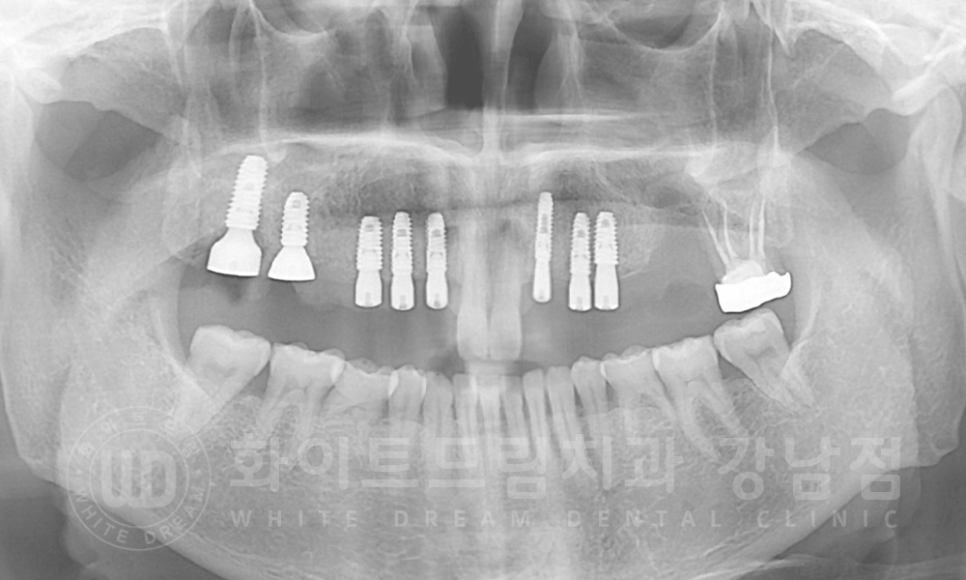

다행히 브릿지를 오래 사용하신 것에 비하면 전체적인 치주 상태는 심각할 정도는 아니었답니다.

골질도 나쁘지 않았고 초기 고정력이 안정적으로 나와 총 8개의 임플란트를 발치 후 당일 식립하고, GBR(골 유도 재생술),

2차 수술까지 한 번에 진행했습니다.

20.06.30 상악 임플란트 8개 식립 & GBR 시행

다만, 26번 치아 자리는 염증이 심해 골 소실도 심한 상태였습니다.

발치 후 해당 공간의 뼈가 차오르기를 3개월가량 기다린 후 수술을 진행하기로 했습니다.

3개월 뒤 26번 치아 잇몸뼈가 차오른 것을 확인한 후 수술에 들어갔습니다.

20.09.08 27번 식립

모든 임플란트 수술이 완료되었고, 이제 임플란트와 잇몸뼈가 잘 유착되면 보철을 세팅하면 치료는 종결됩니다.